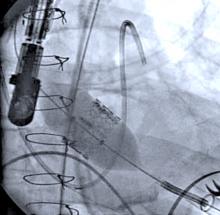

In the United States, radial artery catheterization is performed in the minority of diagnostic angiograms and cardiac stenting procedures despite the benefits it offers to patients in terms of reduced complications and faster mobility after the procedure. However, new data now suggests there might also be a cost savings. Research from the Perelman School of Medicine at the University of Pennsylvania, the University of Washington Medical Center, and the University of Pittsburgh School of Medicine, indicates that radial access may also offer a significant cost savings benefit to hospitals. The findings are published online first in Circulation: Cardiovascular Quality and Outcomes.